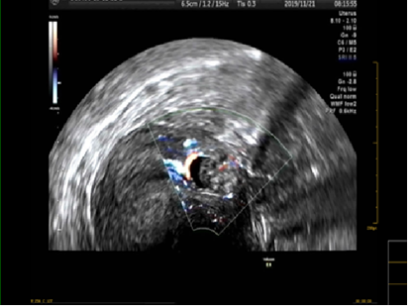

该患者孕囊位于子宫切口处肌壁内,且该处肌层菲薄,厚约3.75px(如图1,2,3)。出血风险及子宫穿孔风险极大。为了保留生育功能,确保患者生命安全,我院妇科积极发起多学科联合诊疗(MDT)会议,特邀请放射科、麻醉科、超声科等相关科室开展讨论,一致决定先由放射科行子宫动脉栓塞术并灌注甲氨蝶呤杀胚治疗(微创介入),72小时之内再行清宫术。最终,该患者在放射科顺利完成甲氨蝶呤灌注和双侧子宫动脉栓塞(如图4-5)的情况下,第二天由妇科在超声科床旁监护下成功完成清宫术(如图6),宫腔镜检查宫腔及切口处无异常。术中出血仅有5ml(出血量较常规清宫术明显减少),并于术后第三天康复出院。

图1:切口妊娠-孕囊与肌层关系

图3:切口妊娠-孕囊血流图像